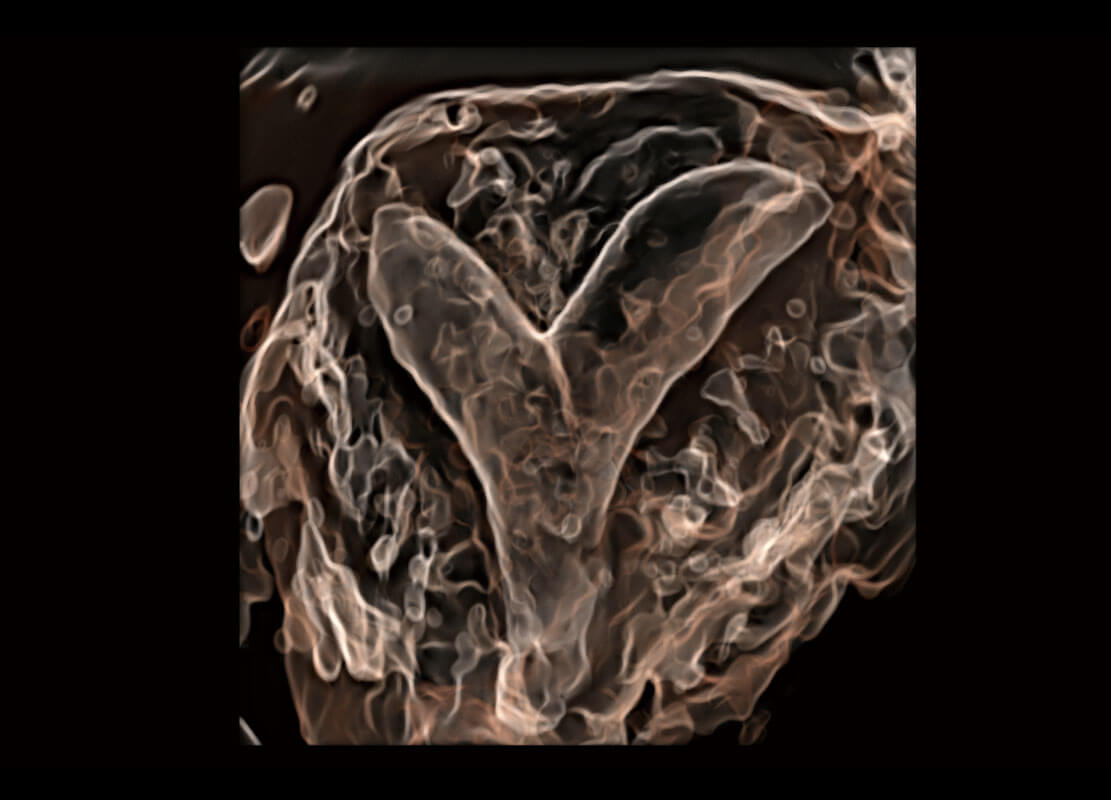

• 胎心容积成像